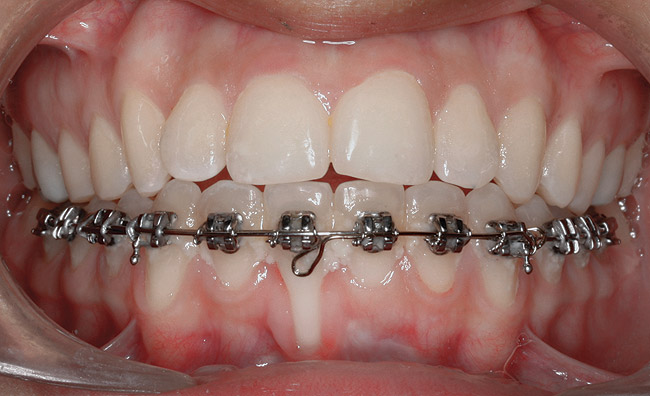

Fig 19. Frontal view showing the orthodontic appliance used in same patient.

Figure 19

Fig 20. Occlusal view after second orthodontic treatment showing corrected B-L inclination.

Figure 20

Fig 21. Frontal view shows narrowing of the GR.

Figure 21